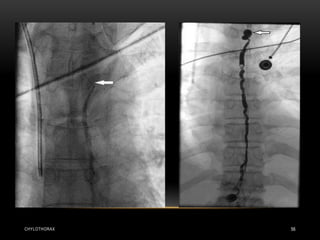

• Basically, a leak can be located non-invasively using

radionuclides or magnetic resonance imaging .

• Lymphography can also demonstrate a leak, but as the only

invasive procedure is rarely indicated nowadays

CHYLOTHORAX 33

• Radionuclide lymphoscintigram

and contrast lymphangiogram

demonstrating a leak in the left

upper mediastinum.

CHYLOTHORAX 32 • Basically,a leak can be located non-invasively using radionuclides or magnetic resonance imaging . • Lymphography can also demonstrate a leak, but as the only invasive procedure is rarely indicated nowadays

CHYLOTHORAX 33 • Radionuclidelymphoscintigram and contrast lymphangiogram demonstrating a leak in the left upper mediastinum.